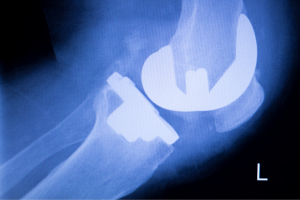

ראשי » קהילה » ניתוח החלפת מפרק הברך - כל מה שצריך לדעת » החלפת מפרק ברך

החלפת מפרק ברך